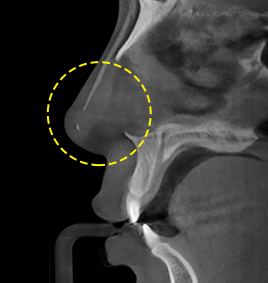

3D-CT nose surgery involves identifying not only the external parts of the nose but also symptoms and causes of nasal bone, crooked nose, nasal septal cartilage, nasal congestion, etc. As three-dimensional analysis using 3D-CT helps establish an adequate surgery plan and reduce damage to blood vessels and nerves, safe and precise operation can be performed.

3D-CT analyzes the nose three-dimensionally.

FACE uses advanced 3D-CT equipment to analyze the overall condition of nasal bone, nasal septal cartilage, skin tissue, asymmetry, etc.,

which cannot be identified by general consultation,

in order to secure safer and more precise nose surgery.